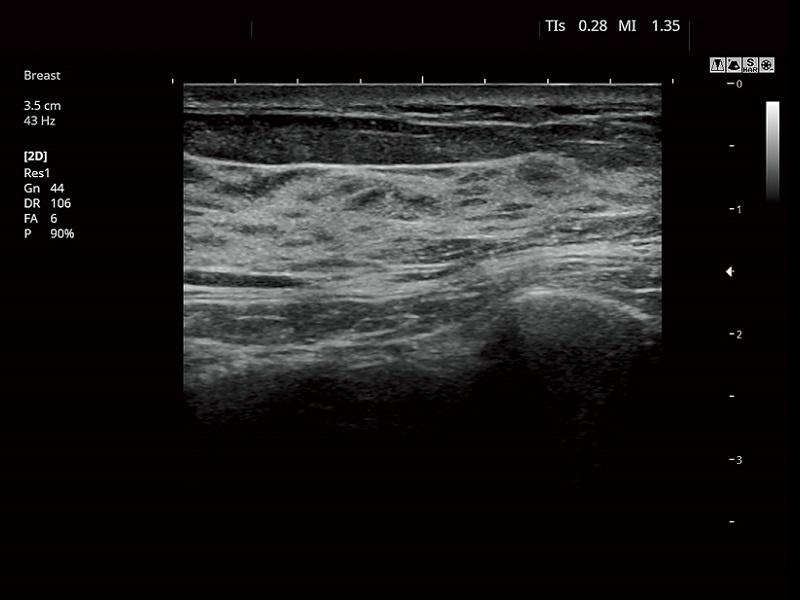

FUJIFILM FUTUS – Ultrasound System

FUTUS features great imaging technologies to support a clear view and confident diagnoses.